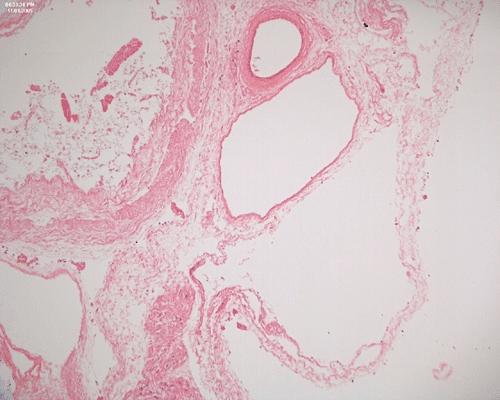

Discussion of the pathology is limited to the alimentary canal. On autopsy, the intestinal loops are largely dilated with gas accumulation. On closer examination, many small, subserosal bubbles can be seen (arrows in Panel A). The intestinal wall is also thinned out as a result of the dilatation by gas (Panel B). In the less affected areas, the intestinal  wall is not thinned out and the mucosa can still be recognized as largely intact (with autolytic changes) (Panel C and E). In the thinned out areas, the mucosa appear pink and necrotic (Panel D, F and G). The subserosal bubbles appear to be empty vesicles filled with air and they are found most frequently in the most necrotic region. In general, these features indicate widespread infarction with gas production (Panel H and I).

Pneumatosis intestinalis, usually limited to the submucosa, is seen in 50% of surgical specimens with NEC.  The gas bubbles have been shown to contain hydrogen, a product of bacterial fermentation.  More than 50% of patients who undergo laparotomy show focal reparative epithelial changes and other evidence of healing, such as the formation of granulation tissue and crypt distortion.  Villous atrophy may also be observed.  Such reparative changes suggest that NEC evolves gradually before a catastrophic event, such as perforation, brings it to clinical attention.